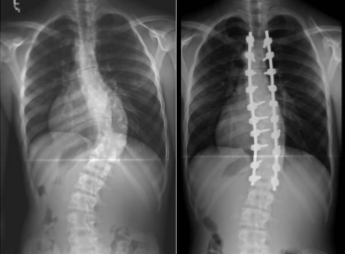

radiology - scoliosis